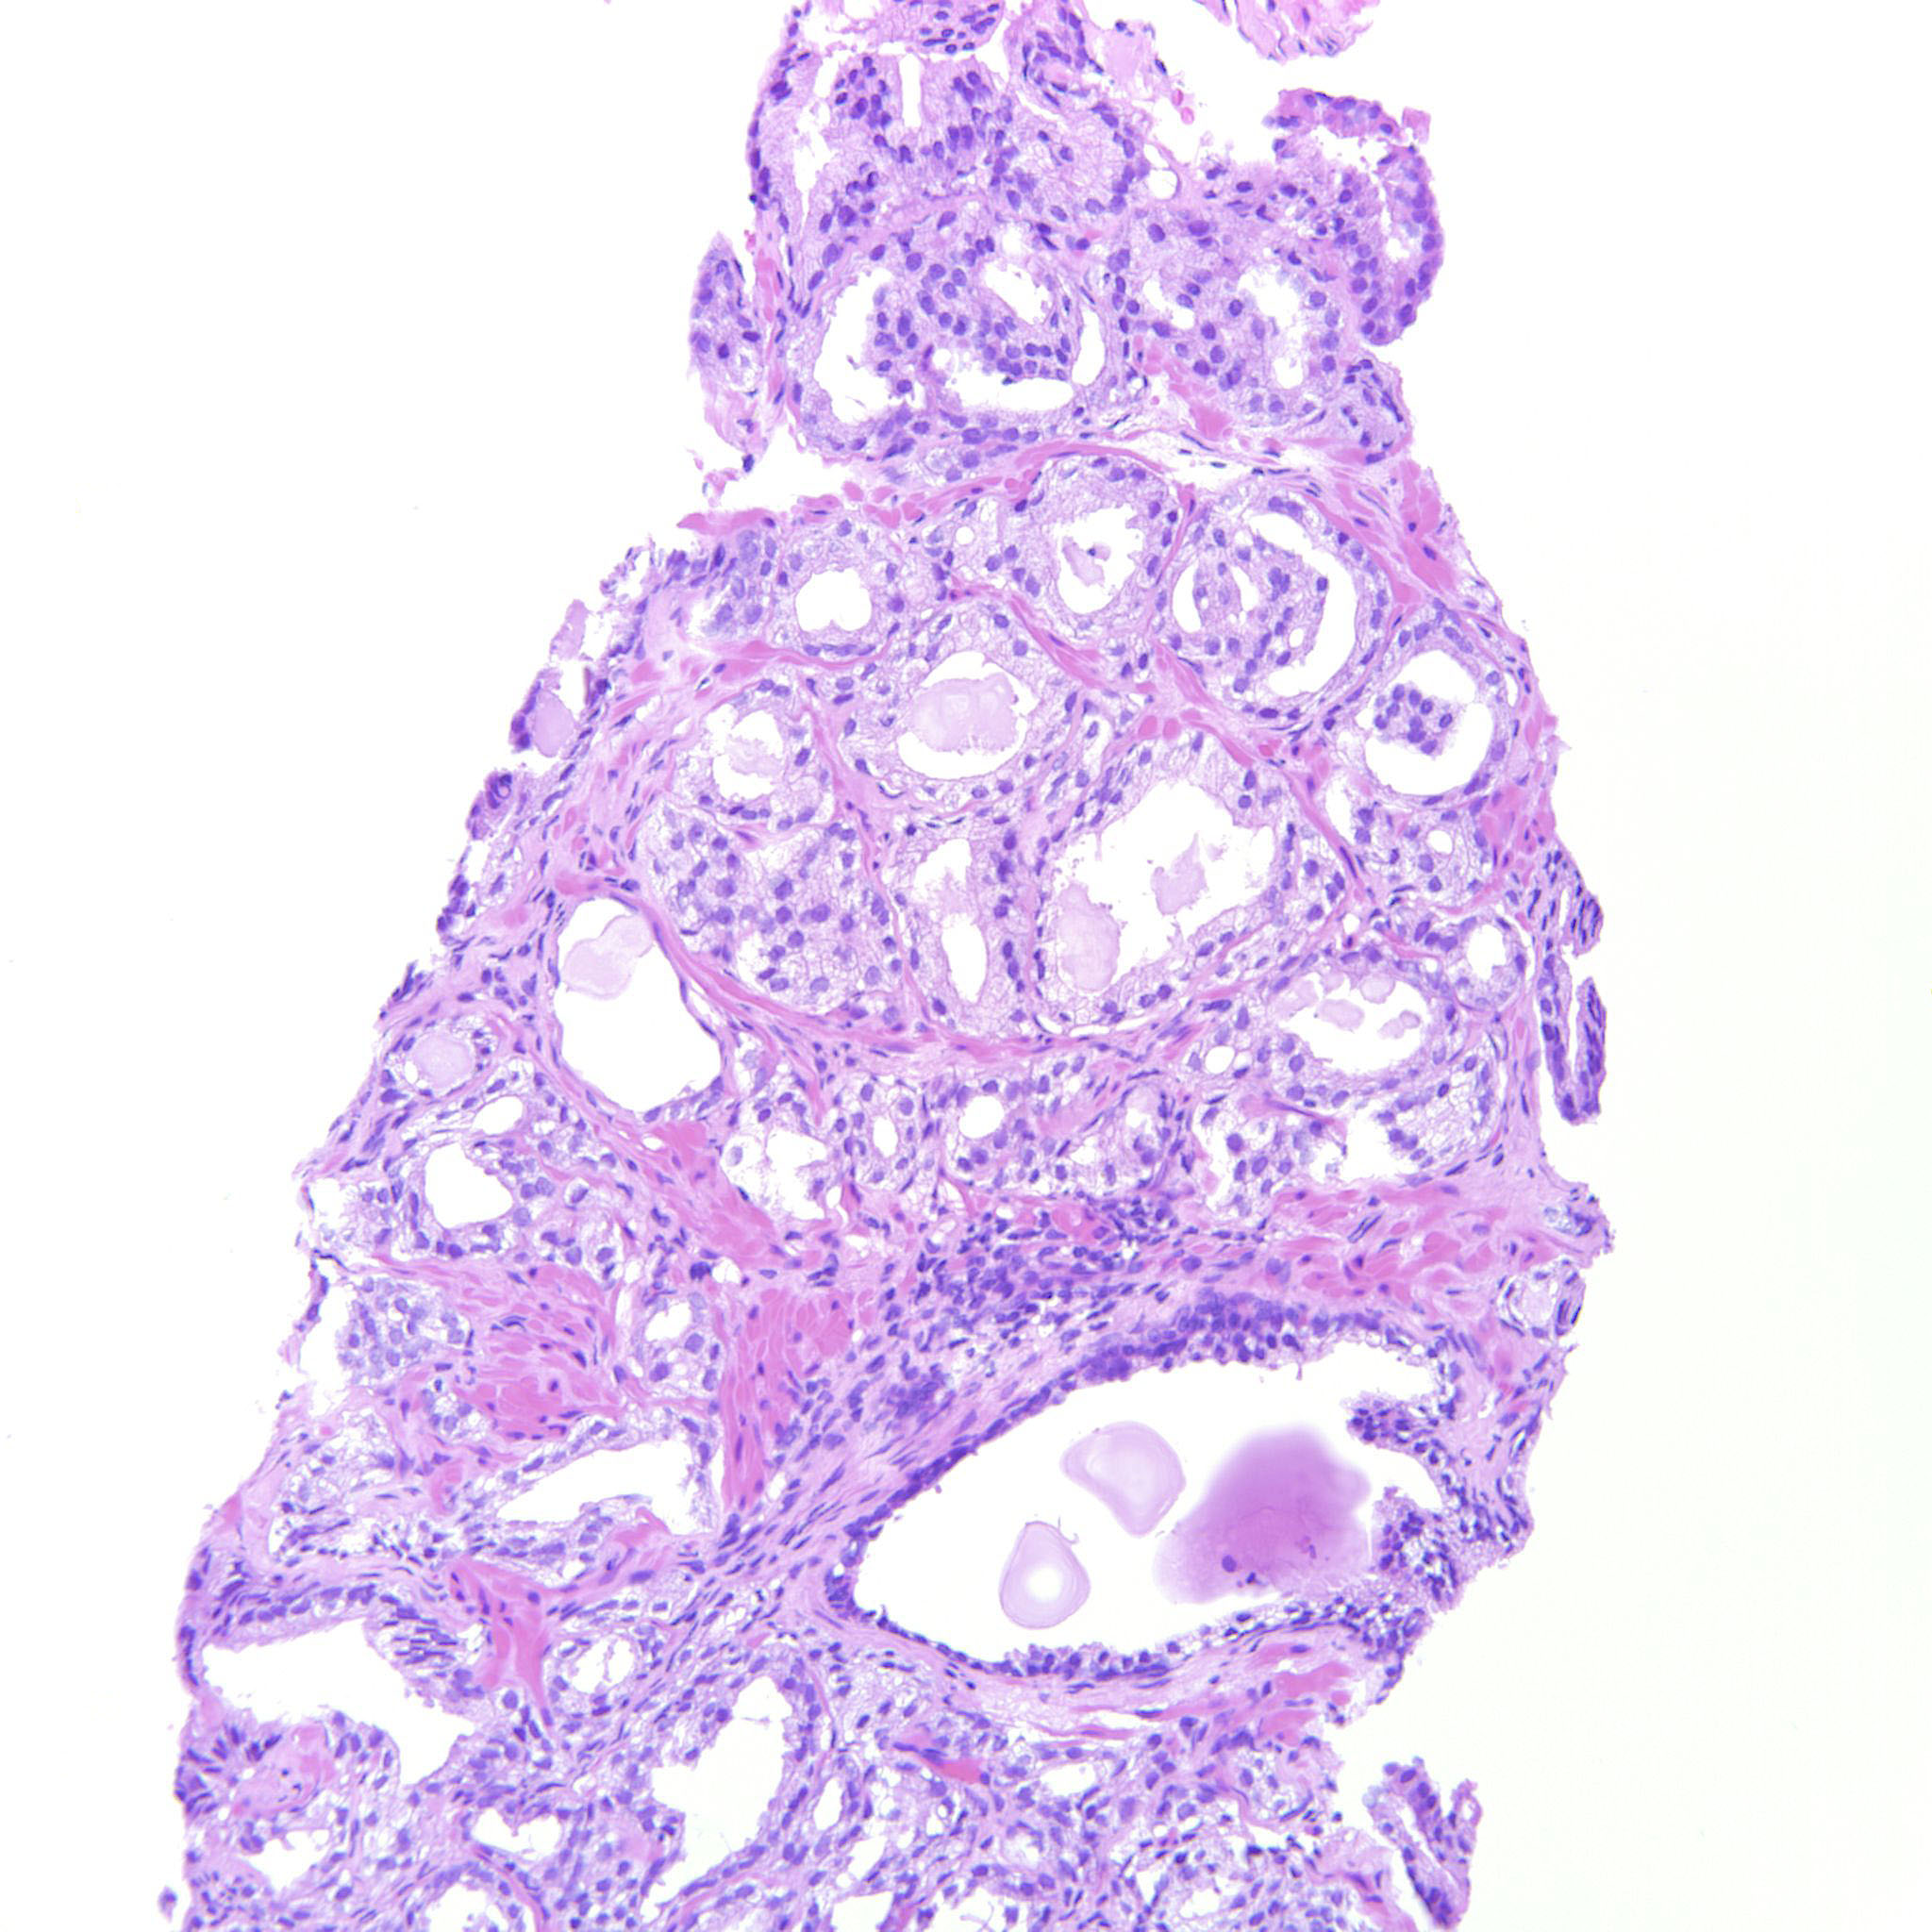

Prostate cancer grading

Case ID: 322